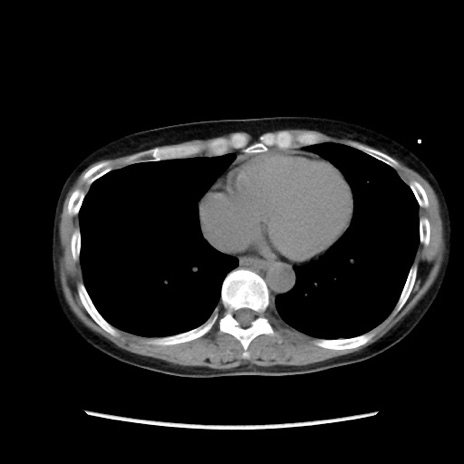

冠状断像

【症例】40歳代 女性

【主訴】上腹部痛、嘔気・嘔吐

【現病歴】約9時間前頃から急に上腹部痛、嘔気、嘔吐が出現。改善しないため救急要請。

【既往歴】子宮頚癌(広汎子宮全摘術、放射線療法)、腸閉塞

【身体所見】腹部:平坦、軟、腸雑音亢進、上腹部を中心に腹部全体に圧痛あり。

【データ】WBC 8400、CRP 0.03